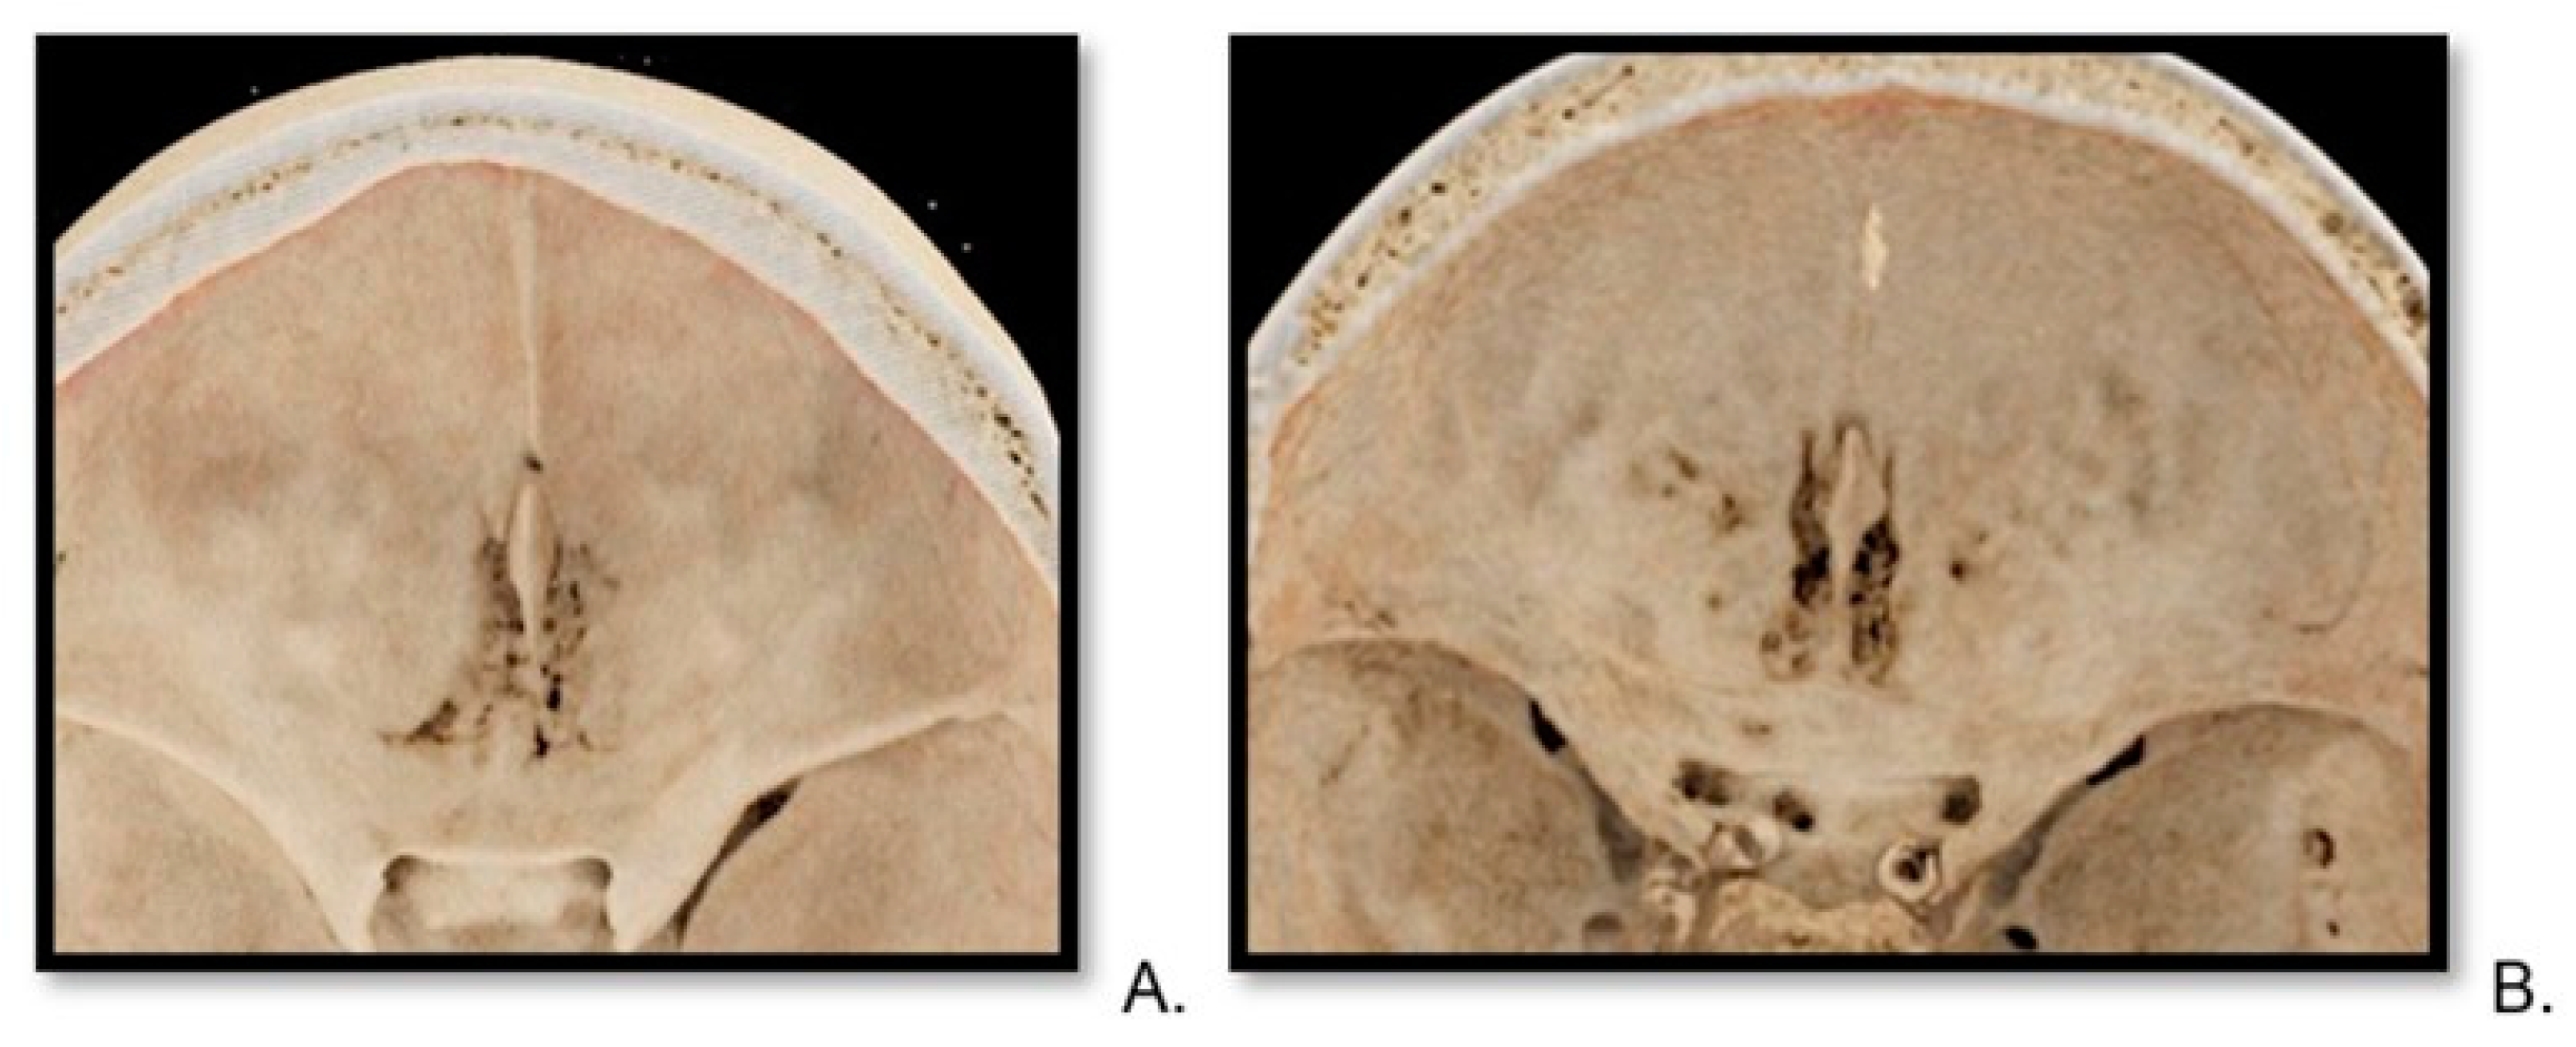

2.4. Image Preparation—Volume Rendering Technique